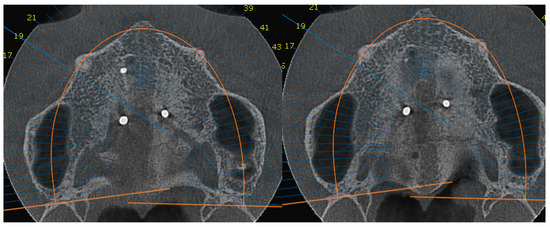

- MARPE therapy associated with cortico-puncture therapy had a positive outcome on midpalatal suture opening and maxillary advancement, but a medium molar inclination of 2.005° was also observed, suggesting that tooth movement cannot be avoided because of the anchorage of the MARPE device at the molar level.

| D’Agnostino & Pearson Omnibus Normality Test | 1st Molar Tilt after Treatment | 1st Molar Tilt before Treatment |

|---|---|---|

| Number of vales | 40 | 40 |

| Minimum | 85.60 | 84.00 |

| 25% Percentile | 87.60 | 85.23 |

| Median | 88.00 | 85.65 |

| 75% Percentile | 88.65 | 86.70 |

| Maximum | 89.30 | 87.90 |

| Mean | 87.88 | 85.87 |

| Std. Deviation | 1.001 | 1.057 |

| Std. Error of Mean | 0.2238 | 0.2363 |

| Lower 95 % CI of mean | 87.41 | 85.38 |

| Upper 95 % CI of mean | 88.34 | 86.36 |

| Table Analyzed | Data 1 |

|---|---|

| Column B | 1st Molar tilt before treatment |

| Vs. | Vs. |

| Column A | 1st Molat tilt after treatment |

| Paired t test | |

| p value | < 0.0001 |

| p value summary | |

| Significantly different? (p < 0.05) | yes |

| One- or two-tailed P value | Two-tailed |

| t, df | t = 12.33 df = 19 |

| Number of pairs | 40 |

| How big is the difference | −2.005 |

| SD of differences | 0.7273 |

| SEM of differences | 0.1626 |

| 95% confidence interval | −2.345 to −1.665 |

| R square | 0.8889 |